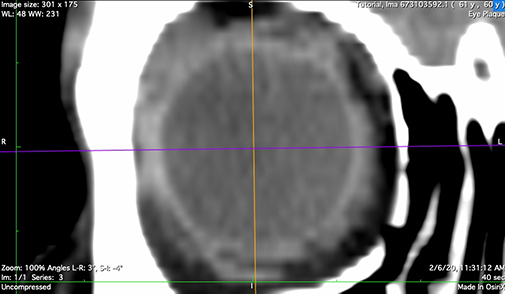

An orbital CT series, using a CT technique optimized for contrast of soft tissues (ie DO NOT use a bone imaging technique) with slice thickness <= 1 mm is the best option to model the eye for posterior and equatorially located tumors. MRI provides an acceptable alternative for ciliary and iris tumors when thin slices are available.

The imaging frame should include both eyes and extend at least a cm or two inferior and superior to the orbits.

An axial imaging frame that includes the involved eye and at least half of the opposite eye is also acceptable as illustrated below.

The orbital CT (or MRI) series is used to create these seven reconstructions that are used to build the 3D model of the eye. That 3D model is used to calibrate the fundus image, measure the optic nerve sheath diameter, and determine suture eyelet coordinates on the eye. If the tumor happens to be large enough to be visible in these reconstructions, the CT also provides confirmation of tumor location, shape and elevation as determined from the fundus and ultrasound imaging.